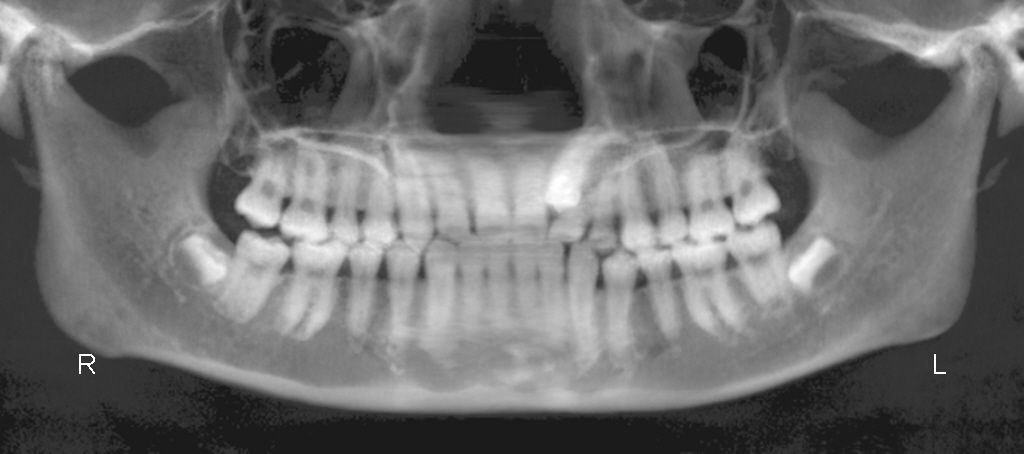

まずは通常のパノラマレントゲンでざっくりとチェックします

さらにCTを撮影して それぞれの根の状態をチェックします